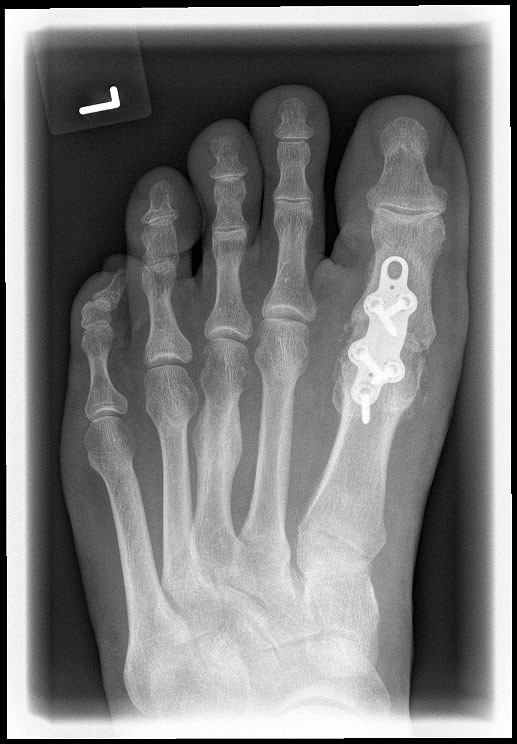

• Röntgenaufnahmen des Vorfußes (unter Belastung) im dorsoplantaren und seitlichen Strahlengang (Abb. 1a+b)

• Beurteilung des Erkankungsstadiums anhand der typischen Arthrosekriterien (Einteilung nach Regnauld) 2

• Beurteilung des Intermetatarsal-Winkels (IMA), des Hallux valgus-Winkels (HVA), mögliche Korrektur der des IMA von 6° durch alleinige Arthrodese, darüber hinaus evtl. zusätzliche MT-I-Korrektur notwendig 101112

• Beurteilung des Metatarsale-Index und der Zehenlänge DI und II, insbesondere nach Voroperationen hinsichtlich einer evtl. notwendigen Verlängerung des ersten Strahls durch Knochenspaninterposition